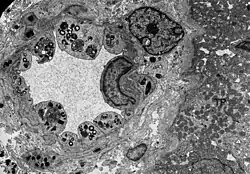

Wie die meisten Symptome bei Morbus Fabry weist auch die Schädigung der Nieren einen progressiven Verlauf auf. Er endet mit dem terminalen Nierenversagen und bewirkt eine deutlich reduzierte Lebenserwartung.[70] Bei dem klassischen Krankheitsbild des Morbus Fabry führen die Gb3-Ansammlungen in den Endothelzellen des Glomerulums, in den Mesangiumzellen, in den Podozyten und in den Zellen des Interstitiums zur Schädigung der Niere.[71] Bei diesen Zellen handelt es sich um ausdifferenzierte Epithelzellen. Auch im Epithel der Henle-Schleife und des distalen Tubulus sowie im Endothel und den Zellen der glatten Muskulatur der Arteriolen der Niere finden sich Glycosphingolipid-Ansammlungen.[72][73] Im Transmissionselektronenmikroskop (TEM) sind die Gb3-Ablagerungen im Zytoplasma gut zu erkennen. Sie haben die Form von Myelinstrukturen und stoßen an den Zellkern. Mit zunehmender Gb3-Akkumulation wird das Mesangium aufgeweitet, worauf eine segmentale oder globale Glomerulosklerose mit Eindickung der Basalmembranen erfolgt.[74] Mikrovaskuläre Läsionen und Schädigungen der für die Filterleistung wichtigen Podozyten sowie der Epithelzellen des Tubulus werden dabei als mögliche Mechanismen diskutiert.[75]

- Gewebeproben aus der Niere von Patienten mit Morbus Fabry

-

Diese lichtmikroskopische Aufnahme zeigt die Akkumulation von Gb3 in den Endothelien des Glomerulums, in den Mesangiumzellen, den Zellen im Interstitium und in den Podozyten. -

Ebenfalls eine lichtmikroskopische Aufnahme. In den Podozyten ist die erhöhte Ansammlung an Gb3 durch eine violette Anfärbung sichtbar gemacht worden. -

Die TEM-Aufnahme zeigt die massive elektronendichte (= schwarze) Ansammlung an Glycosphingolipiden im Lysosom der Podozyten. -

Ebenfalls eine TEM-Aufnahme. Sie zeigt die Inklusionen von Glycosphingolipiden unterschiedlicher Form und Größe in den Zellen des distalen Tubulus. -

TEM-Aufnahme von den Endothelien und Zellen der glatten Muskulatur einer Nierenarteriole mit Inklusionen von Glycosphingolipiden